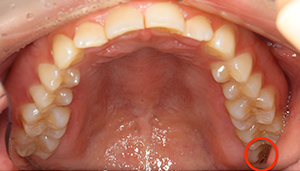

口腔内

- Before

- After

半埋伏の親知らずでした。3糸縫合しました。